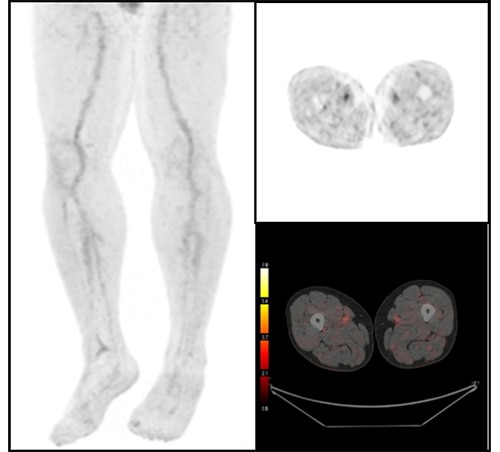

臨床に用いる収集条件は、核医学会が定める「18F-FDGを用いた全身PET撮像のためのファントム試験手順書」に準じたNEMA IEC Bodyファントムによる物理評価と、実際に診断するPET核医学専門医師の視覚評価(図4、図5)により決定しました。運用開始当初は、1bed 120秒撮像、Q.Clear β400で再構成を行っていましたが、収集時間をもう少し短く出来るのではないかと考え再検討し1bed 90秒撮像、Q.Clear β500の再構成としました。Precision DL(PDL)は、元の画像の特徴を大きく変えずにノイズが除去できるMediumを使用しています。

図4. 撮像時間90s

図5. 撮像時間120s